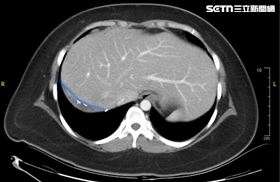

免驚!孝女捐70%肝救父 術後1個月全長回

彰化一名60歲的父親,因長期受C型肝炎與酒精性肝硬化...